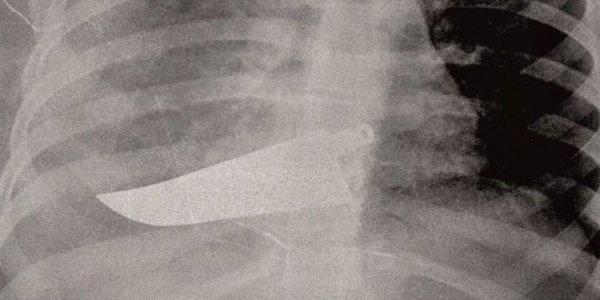

Σοκάρουν οι ακτινογραφίες από περιστατικά επιθέσεων κατά γυναικών - Εγκαύματα, μελανιές, σπασμένα οστά, σημάδια στραγγαλισμού, μαχαίρι στην πλάτη

Με αφορμή την Ημέρα, η ιταλική «La Repubblica» φιλοξένησε την γιατρό Μαρία Γκαρσία Βανταντόρι σε ένα εξαιρετικό αφιέρωμα το οποίο δημοσίευσε ακτινογραφίες γυναικών που έχουν πέσει θύματα ενδοοικογενιακής βίας.

Η Μαρία Γκράτσια Βανταντόρι είναι χειρουργός επί 26 χρόνια στο μιλανέζικο νοσοκομείο Σαν Κάρλο. Με πρωτοβουλία της πραγματοποιείται μια έκθεση ακτινογραφιών κακοποιημένων γυναικών.

Η ίδια αναφέρει πως στις ακτινογραφίες των θυμάτων αντικατοπτρίζεται η καθημερινή φρίκη που αντιμετωπίζει με τους συναδέλφους της στα «Επείγοντα».

«Συχνά οι τραυματισμένες γυναίκες δεν έχουν τη δύναμη να πουν τι τους έχει συμβεί, αλλά τα σώματά τους και τα τραύματά τους μιλούν από μόνα τους», σημειώνει, μιλώντας στην ισπανική εφημερίδα.

Σύμφωνα με την ίδια, καθημερινά καλούνται να αντιμετωπίσουν «σπασμένα οστά σε μύτη, χέρια, πόδια, πληγές από μαχαιριές, εγκαύματα, μελανιές και άλλα σημάδια στραγγαλισμού».

Κάνει λόγο μάλιστα και για περιστατικό, όπου ασθενής εμφανίστηκε με μαχαίρι στην πλάτη, που όμως το περιστατικό δηλώθηκε ως «ατύχημα» στο νοσοκομείο.

«Όλα αυτά τα χρόνια έχω δει χιλιάδες ακτινογραφίες γυναικών με κάθε είδους τραύματα, ακόμη και πολύ σοβαρά. Πολλές από αυτές τις κακοποιημένες γυναίκες αρνήθηκαν ότι τα τραύματά τους προκλήθηκαν από τους συζύγους ή άλλα μέλη της οικογένειάς τους. Η άρνησή τους σχετίζεται με συναισθήματα όπως φόβος, ντροπή, αγωνία για την τύχη των παιδιών τους ή και για τη ζωή τους ακόμη», σημειώνει η γιατρός.